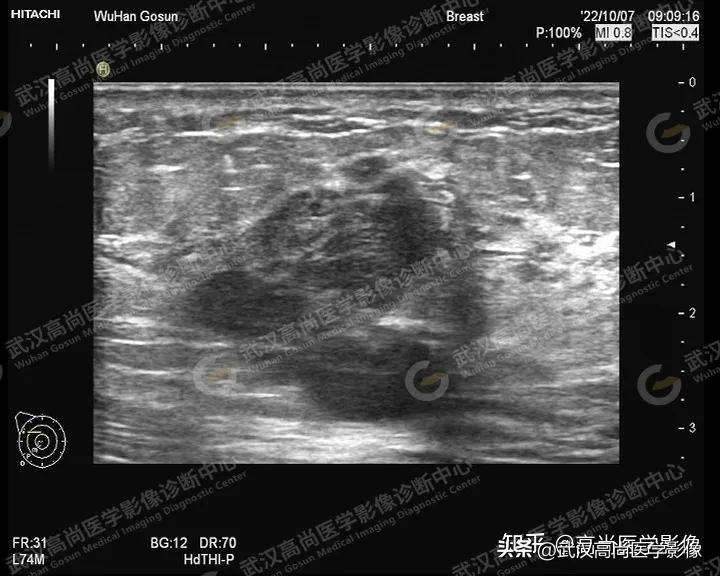

患者一:

女,48岁,外院体检发现乳腺包块,来本中心进一步检查。主诉无不适。

超声影像如下:

图一

图一、图二、图三:右侧乳腺10点钟方向实性肿块,形态不规则,轮廓不规整,成角,大小约33x24x28mm,内部回声不均匀,内部见散在点状钙化,内血流信号丰富。